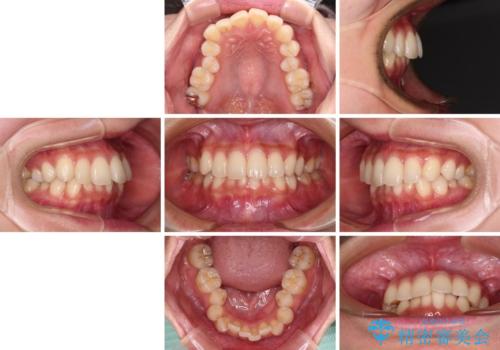

- 前歯のデコボコと強い咬みしめを気にして来院された患者様です。

インビザラインを用いて、前歯の叢生を解消するとともに、ディープバイトを改善していくこととしました。

海外へ転居する予定があったため、1日22時間以上の装着時間をしっかりと守っていただき、予定期間よりも早く、思っていた以上にきれいに仕上げることができました。